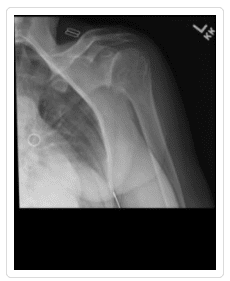

Osteoarthritis (degenerative joint disease) is an orthopedic injury that occurs when the cartilage that protects and allows the joints to move begins to wear down or degenerate, potentially causing the bones of the joints to scrape against one another with every movement. Shoulder osteoarthritis (OA) is a shoulder injury that is most common among people who are over the age of 50 after years of wear and tear on the joint. Younger adults experience osteoarthritis of the shoulder either as a result of hereditary predisposition or from an injury or trauma to the shoulder, such as dislocation. This arthritic condition is particularly common in people who work in jobs that require repetitive movements and physical activity, such as athletes or construction workers.

Total Shoulder Arthroplasty – A shoulder joint replacement surgery involves removing damaged bone and tissue and replacing them with artificial pieces or prosthesis. The procedure may involve only replacement of the head of the humerus bone or replacement of the entire ball and socket (glenoid) joint. The artificial components, made of metal or plastic, may be cemented into place or “press fit” into the socket if the bone is still in good condition.

Hemiarthroplasty – Also known as a partial replacement, a hemiarthroplasty involves replacing the humerus or arm bone with a prosthetic metal implant while the shoulder joint is left more or less intact. The shoulder osteoarthritis procedure may involve replacing the head of the humerus with a metal ball and stem as well as the arm bone or simply resurfacing the humerus head with a prosthesis that fits over the bone like a cap, preventing further wear and tear.